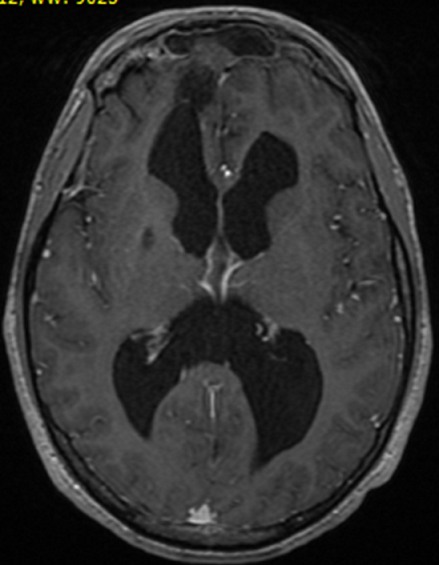

Une méningocèle est une saillie des méninges à travers des points de faiblesse, habituellement dans la base du crâne. Elle peut être congénitale, iatrogène ou spontanée. Elle est le plus souvent asymptomatique mais peut parfois se manifester par une rhinorrhée, une otorrhée, ou des signes de méningite bactérienne récurrente. L'association à une neurosarcoïdose est exceptionnelle. Patient âgé de 37 ans, a consulté pour une rhinorrhée récidivante évoluant depuis un an. Il s'agissait d'un patient suivi depuis deux ans pour une sarcoïdose systémique dont le diagnostic a été retenu devant l'association d'une xérostomie, un lupus pernio, une pneumopathie interstitielle, une alvéolite lymphocytaire et une granulomatose sans nécrose caséeuse à la biopsie labiale et bronchique étagée; et dont le traitement s'est basée sur une corticothérapie générale avec bonne évolution clinique. L'examen physique a montré une muqueuse nasale saine. Le patient n'avait pas de syndrome méningé. L'examen ophtalmologique était normal. L'analyse du liquide nasal a confirmé qu'il s'agissait d'un liquide céphalo-rachidien. L'examen biologique et la biopsie de la muqueuse nasale étaient sans anomalies. La TDM cérébrale a révélé l'image d'une méningocèle associée à une hydrocéphalie. Le diagnostic d'une hydrocéphalie compliquant une sarcoïdose chez un patient porteur d'une méningocèle a été retenu. Le traitement s'est basé sur un traitement chirurgical de la méningocèle et un traitement médical qui a consisté en une corticothérapie associée à des boli de cyclophosphamide. L'évolution était marquée par une bonne évolution clinique et radiologique et l'absence de récidive de la rhinorrhée.